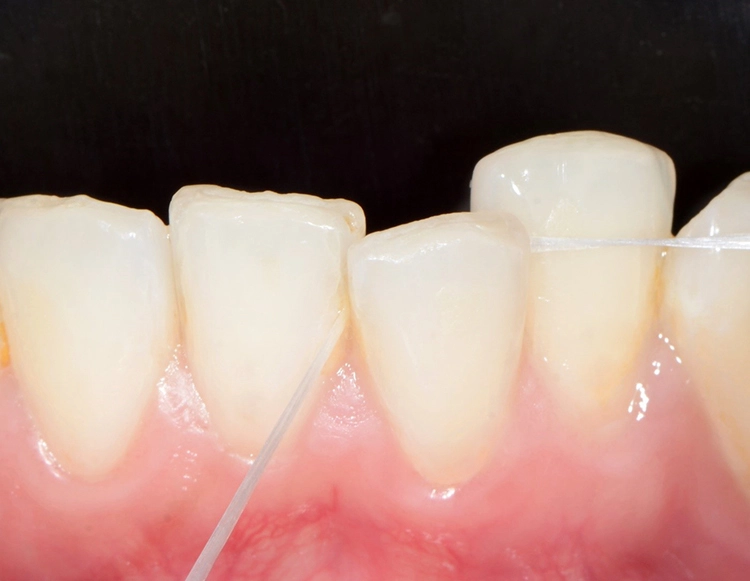

In der Praxis werden an Patienten zuweilen mit Messsonden diverse Größen ausprobiert, um eine entsprechende Empfehlung abzugeben [26]. Allerdings ist ihr Wert umstritten. Eine korrekt angepasste Interdentalraumbürste sollte den kompletten Interdentalraum reinigen und mit „mittlerem“ Druck ein- und auszuführen sein. Wenn sie zu dünn ist, hat sie eine zu geringe Reinigungswirkung; ist sie hingegen zu dick, besteht Traumatisierungsgefahr. Abbildung 2 zeigt die Einprobe und Auswahl am Beispiel des Interdentalraums 41/42.